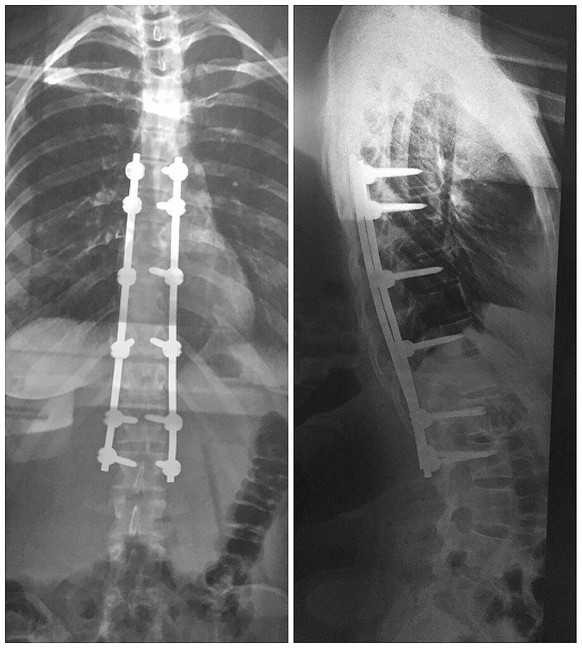

Die 16-Jährige unterzeichnet die Einwilligungserklärung. Danach folgt die heikle Operation. Spezielle Titan-Schrauben mit Halterungen werden in die Wirbelkörper geschraubt. Danach führen die Spezialisten Metallstäbe ein, um die Wirbelsäule aufzurichten. Um Naomis Wirbelsäule geradezubiegen, braucht es 12 Schrauben und 2 Stangen à 25 Zentimetern, die ihr ein Leben lang erhalten bleiben sollen. Der Eingriff verläuft ohne Komplikationen.